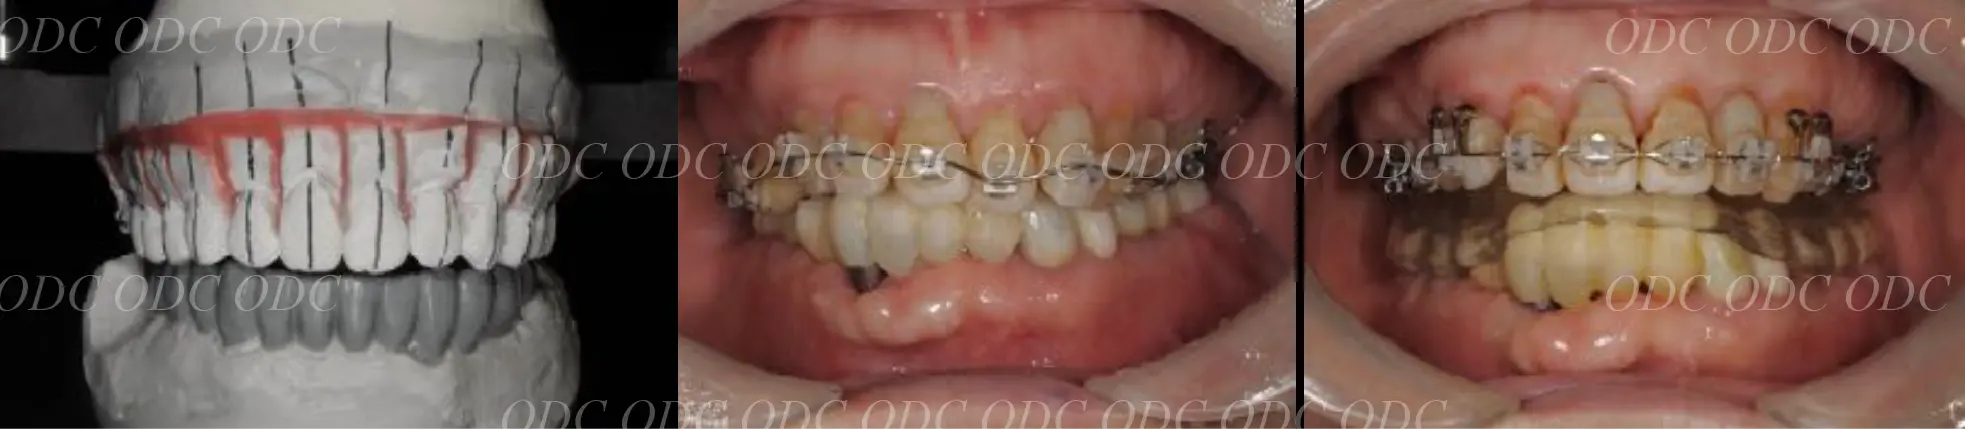

上顎天然歯に関しては矯正治療、下顎にはフルマウスのインプラント治療を計画致しました。

顎関節の安定を確認した後、矯正治療とインプラント治療を並行して行いました。

約3年の治療期間を経て、計画通りの満足のいく結果を獲得することができました。

2014年、治療終了時の口腔内の状態です。

インプラント上部構造はCADCAMによって作成されたジルコニアの上部構造です。